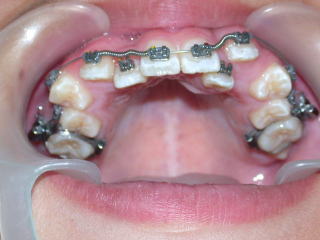

平成18年7月25日 矯正装置装着